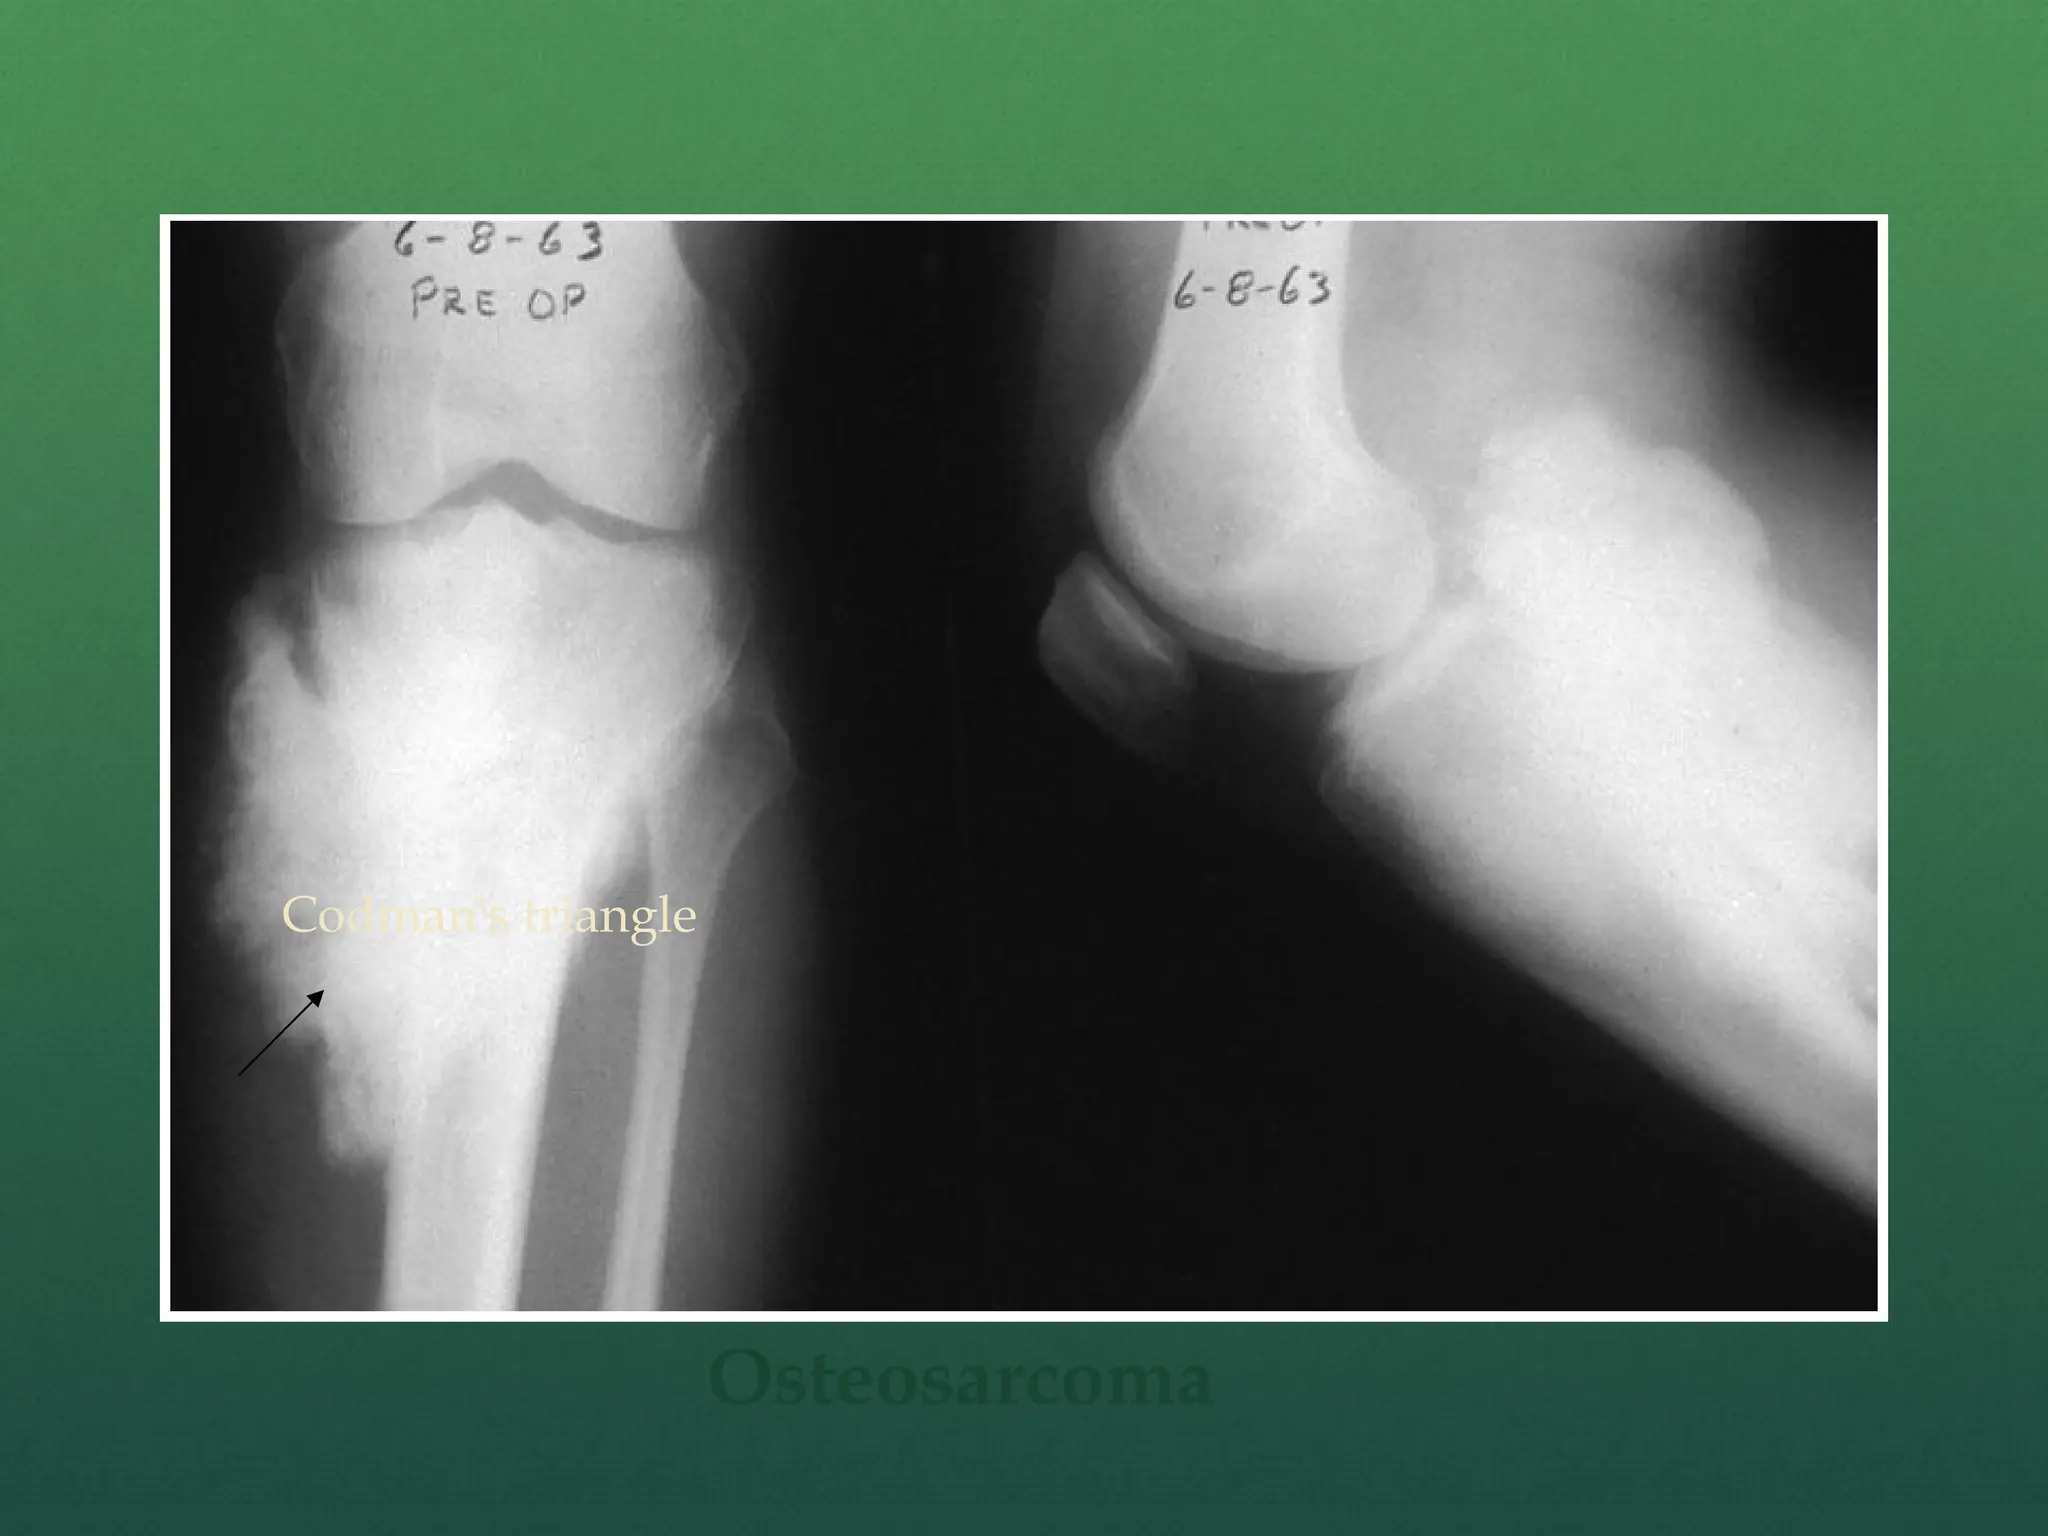

 Classic X-ray findings:

1. Codman's triangle (periosteal elevation)

2. Sunburst pattern/Sunrays appearance

3. Bone destruction

4. Ill-defined margins

Codman’s

triangle

Sunrays

appearance

Osteosarcoma

Codman's triangle